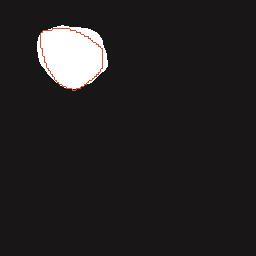

基于逐通道空间自适应选择核卷积与双向边界感知机制的乳腺超声图像病变分割网络

A Breast Ultrasound Images Lesion Segmentation Network Based on Channel-Wise Spatially Adaptive Selective Kernel Convolution and Bidirectional Boundary-Aware Mechanism

乳腺癌是全球女性最常见的恶性肿瘤之一,准确的病变分割对于乳腺癌的早期诊断与治疗具有重要意义。然而,由于病变形态的多样性以及超声成像机制的复杂性,现有基于深度学习的乳腺超声图像病变分割方法在分割准确性方面仍面临巨大挑战。为进一步提升乳腺超声图像中病变区域的分割精度,该文基于经典U-Net架构,提出了一种新型乳腺超声图像病变分割网络(CWSASKM-BBAM-Net)。首先,在网络中引入逐通道空间自适应选择核卷积模块(CWSASKM),根据不同通道的语义特征为每个空间位置自适应选择感受野大小,以增强多尺度信息的建模能力;然后,引入双向边界感知机制(BBAM),通过融合正向与反向注意力,对目标显著区域及其边界进行协同建模,同时逐步提升对非显著区域与病变区域的区分能力,以进一步强化边界信息的表达;最后,在3组公开乳腺超声图像数据集(BUSI、UDIAT和STU)上开展分割实验。结果表明:该方法在数据集BUSI上的杰卡德指数、精确率、召回率和Dice相似系数分别为71.97%、82.85%、81.40%和80.44%,较次优方法分别提升1.69、1.05、1.28和1.84个百分点;在数据集UDIAT上,这4项指标分别达到78.14%、88.31%、86.73%和86.10%,较次优方法分别提升了2.75、2.04、0.56和2.01个百分点;在外部数据集STU上,该方法也取得了优于其他方法的整体表现。实验结果表明,CWSASKM-BBAM-Net在乳腺超声图像分割任务中展现出更优的整体性能。